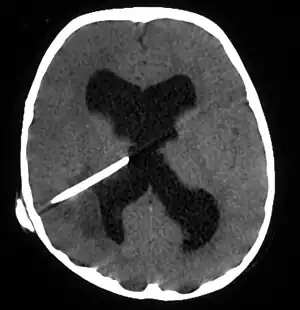

| Brain abscess in a person with a CSF shunt.[1] | |

The diagnosis is established by a computed tomography (CT) (with contrast) examination. At the initial phase of the inflammation (which is referred to as cerebritis), the immature lesion does not have a capsule and it may be difficult to distinguish it from other space-occupying lesions or infarcts of the brain. Within 4–5 days the inflammation and the concomitant dead brain tissue are surrounded with a capsule, which gives the lesion the famous ring-enhancing lesion appearance on CT examination with contrast (since intravenously applied contrast material can not pass through the capsule, it is collected around the lesion and looks as a ring surrounding the relatively dark lesion). Lumbar puncture procedure, which is performed in many infectious disorders of the central nervous system is contraindicated in this condition (as it is in all space-occupying lesions of the brain) because removing a certain portion of the cerebrospinal fluid may alter the concrete intracranial pressure balances and causes the brain tissue to move across structures within the skull (brain herniation).

Ring enhancement may also be observed in cerebral hemorrhages (bleeding) and some brain tumors. However, in the presence of the rapidly progressive course with fever, focal neurologic findings (hemiparesis, aphasia etc.) and signs of increased intracranial pressure, the most likely diagnosis should be the brain abscess.